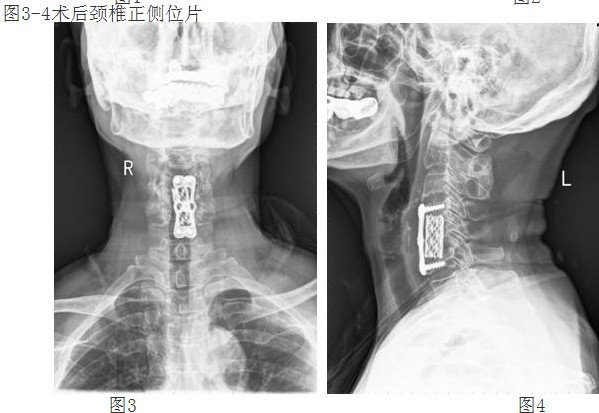

经过谭主任和全科医护人员充分的术前准备和讨论,对患者实施了颈椎前路颈4/5、颈5/6椎间盘摘除、颈5椎体次全切除、椎管减压钛网植骨融合、颈前路钛板固定术。手术取得了成功。术后第二天,李阿婆的四肢麻木就明显减轻,握手能力和手臂力量都明显好转。

经颈前路减压植骨融合内固定术属复杂高难度高风险手术,该技术的成功开展,填补了我院在该领域的空白,表明我院脊柱外科技术迈上了更高的台阶。(后附典型病例照片)